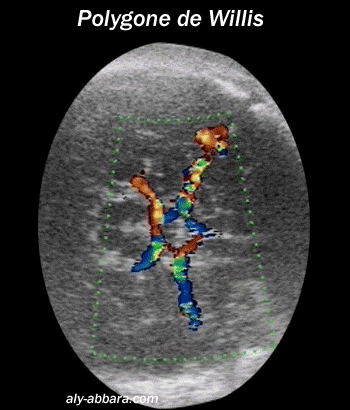

Polygone de Willis

les artères cérébrales antérieures, moyennes et postérieures

(grossesse de 35 SA)